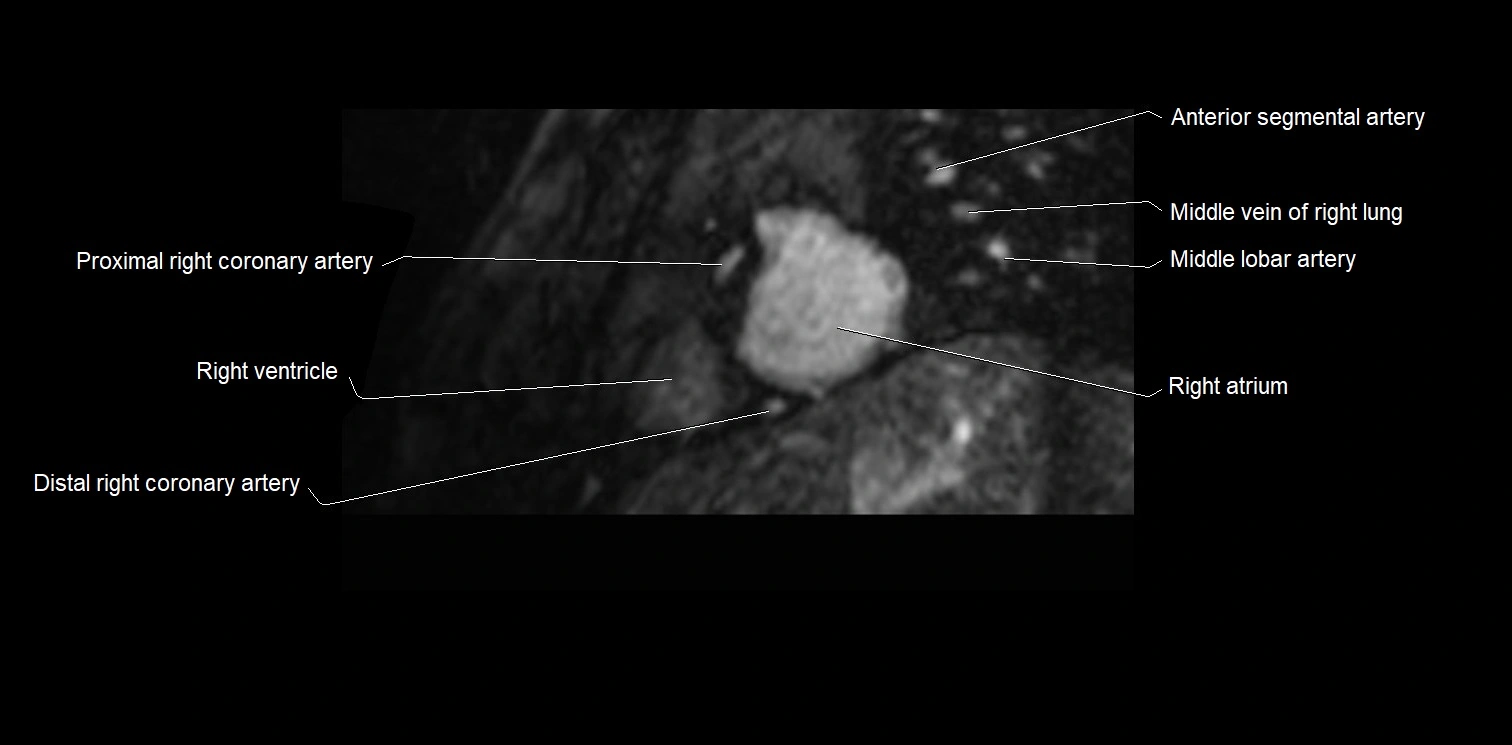

MRI image